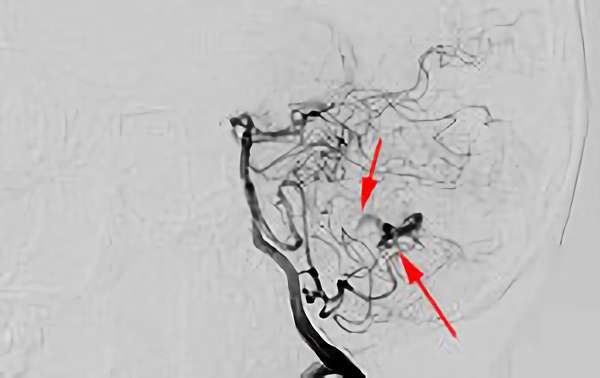

No.1620 手術後